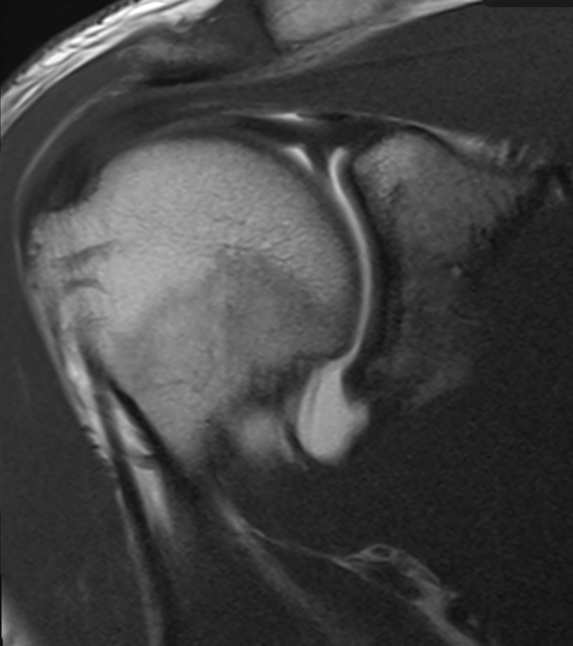

Sublabral recess and Buford complex